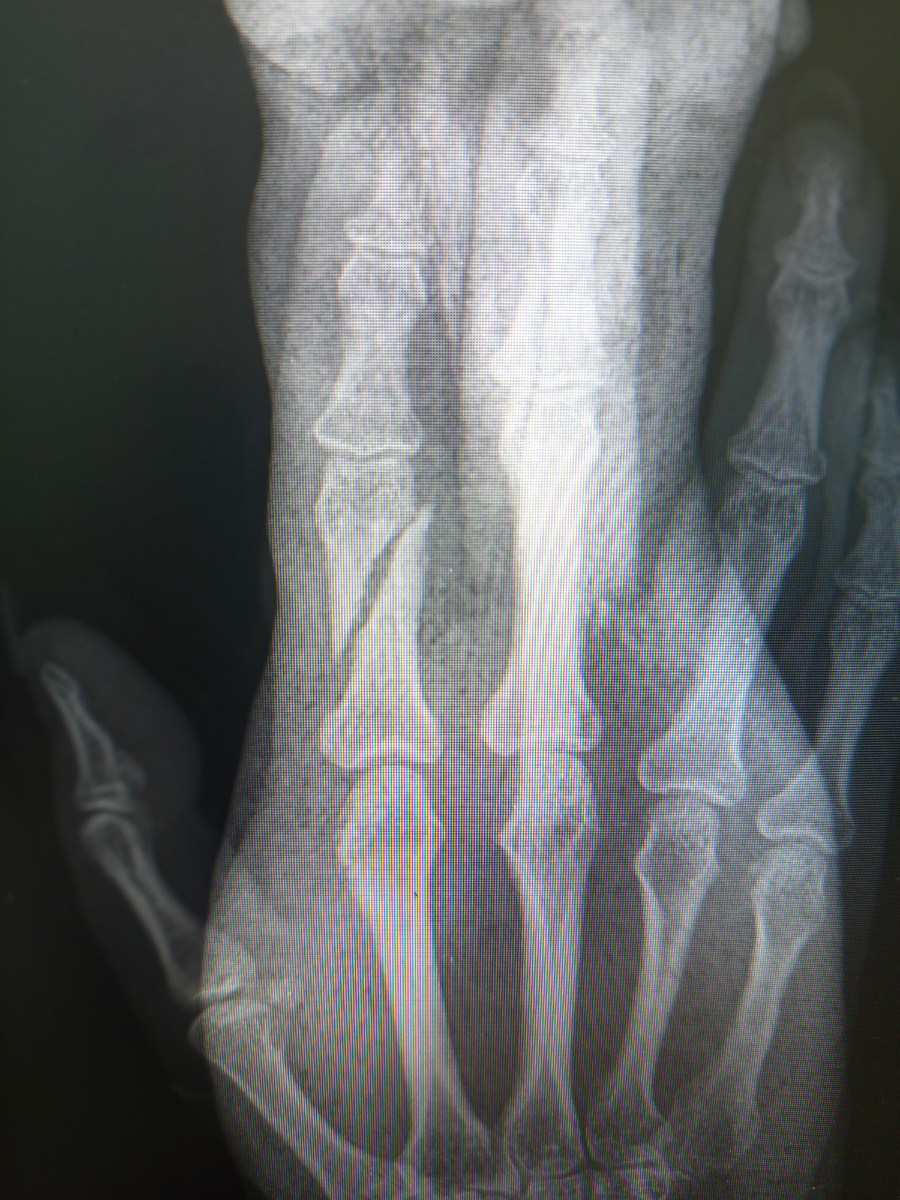

Пришла пациентка , рука с лангеткой, лоб заклеен пластырем.

Да , палец сломала , неудачно при чем.

Сломана у девушки локтевая кость.

Предупредила пациентку, что это не вывих,что косточка все-таки сломана, чтобы активно рукой не пользовалась до гипса.